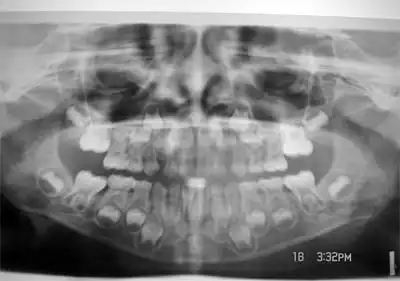

Vor jeder kieferorthopädischen Behandlung muss eine ausführliche Diagnostik erfolgen. Diese besteht aus einer ausführlichen allgemein- und zahnärztlichen Anamnese sowie der ätiologischen Beurteilung der Patientensituation. Anschließend folgt die klinische Untersuchung, eine Funktionsanalyse, Modellanalyse und eine fernröntgenologische Untersuchung. Mit Hilfe dieser Untersuchung wird die Kieferrelation, die Lagebeziehung zwischen dem Oberkiefer und Unterkiefer, dargestellt. Gleichzeitig werden die dentoalveolären Befunde erhoben und das Dentitionsstadium festgestellt.[4]